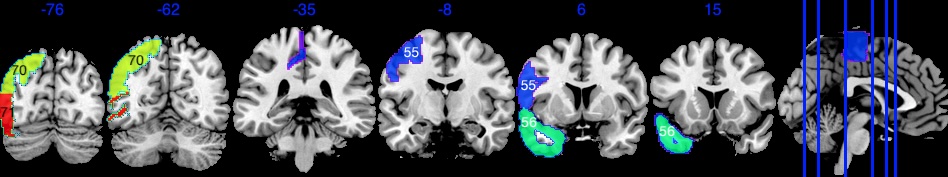

The amygdala region is part of the limbic system. They are responsible for detecting danger and negative emotions, and play an important role in behavior, emotional control, and learning (Bzdok et al., 2013). The emotion task fMRI data in UK Biobank is based on emotion tasks where participants are asked to identify faces with negative emotions. Hence we expect the amygdala region to play an important role. The amygdala region is a small area in the brain, as shown in Figure 4(a), containing 380 voxels out of a total of 121,865 voxels.

Based on the results shown in Figure 4, SBIOSimp identifies a large proportion of voxels in the amygdala region to be active. Numerically, SBIOSimp identifies 324 out of 380 voxels in both the left and right amygdala to be active with . From the highlighted box in Figure 4(b), the active voxels mostly concentrate on the direction where the amygdala region connects to the parahippocampal gyrus, anterior division. The anterior portion of the parahippocampal gyrus is involved in complex emotive processes and has significant interconnectivity with other cortical limbic structures and the amygdala (Kaas, 2016). Figure 4(c) shows the yellow-shaded area within the amygdala in which voxels are associated with at least 50% decline in the brain signal intensity for 10-year increase in age from 50.

The true is generated in Figure 19(a), a smooth function over pre-specified regions 55,56,70,71. Here, is simulated as , where is the dimension of , and is the geometric center of all voxels in regions 55,56,70,71. Any values in below 0.1 are thresholded to 0, so that the active area is contained in regions 55,56,70,71, but does not span over all voxels in regions 55,56,70,71 (this can be seen in the second to left slide [-62] in region 70, where the top voxels in Figure 19(a) within region 70 are 0). To ensure smoothness, we use this exponential square function to generate , but this function is different from the GP kernel used in UKB analysis, where we used Matèrn kernel for each region and tuned the kernel parameters so that the estimated covariance can be similar to the empirical covariance of the observed data. The simulation study uses the same kernel as in the UKB analysis, without knowing any information about the smoothness in the true signal or using any fine-tuning according to the observed images.

The location of the four regions is highlighted in Figure 19(c). Based on Figures 19(a) and 19(c), is generated with smoothly varying functional values across the region boundaries of region 55 and 56, and region boundaries of region 70 and 71.